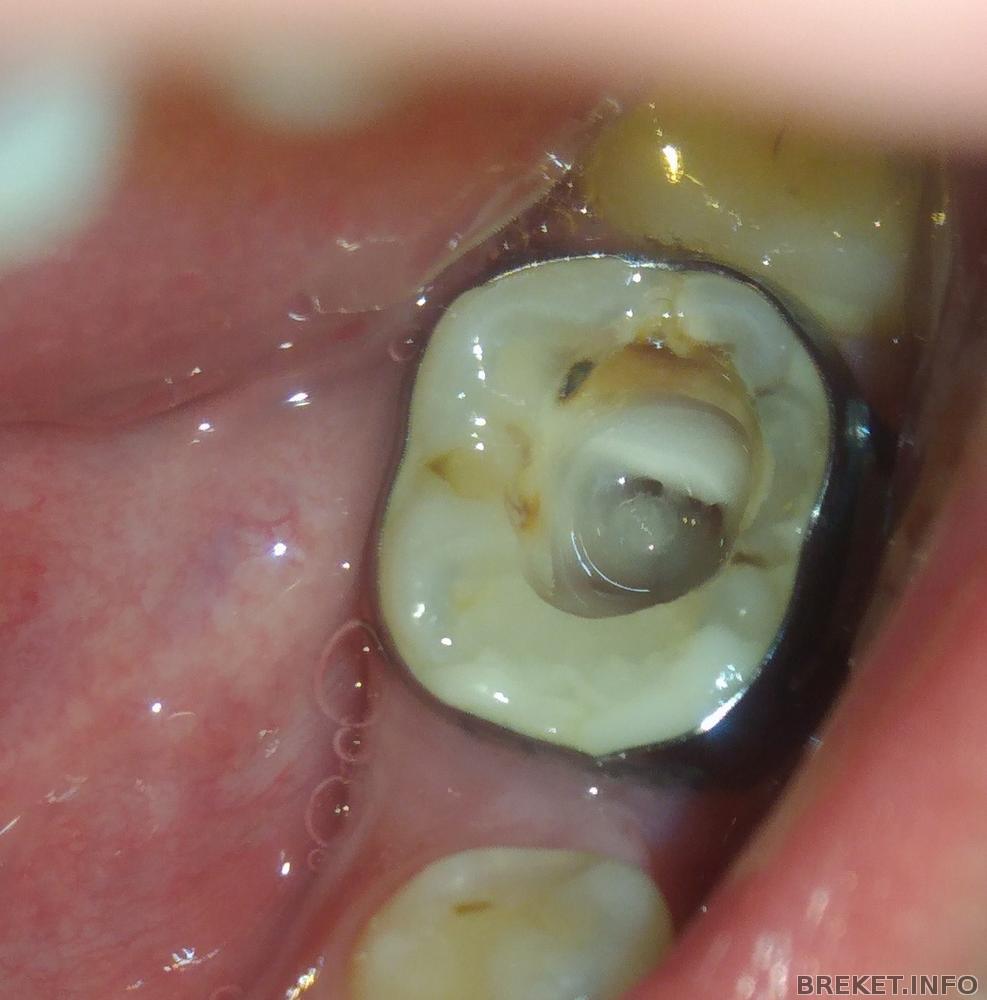

Мне вскрыли пломбу,убрали гной(флюс был) ,промыли каналы и я с лазером посидела) ахахаха

Задняя и внешняя сзади стенка зуба слабовата, я б на месте стоматолога настаивал на коронке.

Кстати там то что я и подозревал, кариес из под кольца дошел до пульпы, там с задней внутренней стороны черная точка - оно самое, почему я и говорил что нужно снимать кольцо.

периодонтит у меня. Сегодня промыли каналы и под лазером посидела. Но т.к. на зуб еще нажимать больно,но при этом боль уже не такая сильная,расширять каналы сегодня не стали,должны завтра

по пломбам я тоже согласен - ИМХО халтура на от...сь сделана, стык между материалом и зубом обычно не виден + пломба должна повторят контуры зуба с углублениями и буграми - иначе и пища не жуется как надо и верхний зуб просто раздавит ее и она треснет.